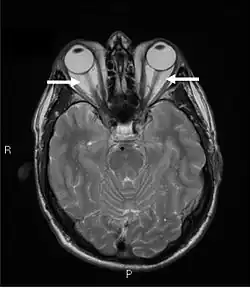

Das Ausmaß des Exophthalmus lässt sich mit einem augenheilkundlichen Untersuchungsgerät, dem sogenannten Exophthalmometer, quantifizieren und erlaubt somit auch die Dokumentation von Verlauf und Status. Raumfordernde Prozesse und Platzverhältnisse in der Orbita können mit bildgebenden Verfahren (Ultraschall, CT, NMR) dargestellt werden. Eine Untersuchung von Gesichtsfeld und Sehschärfe erfolgt mittels Perimetrie und Sehtests.

Weitere diagnostische Maßnahmen dienen primär der Erfassung des Schwere- und Aktivitätsgrades der Krankheit sowie drohender Komplikationen.[29] Insbesondere zur Abschätzung der entzündlichen Aktivität eignet sich die Untersuchung mittels Kernspinresonanzspektroskopie (NMR).[30]

Differentialdiagnostisch ist mittels verschiedener bildgebender Verfahren (Computertomographie, NMR) neben einem hinter dem Auge gelegenen Tumor auch das Krankheitsbild einer okulären Myositis auszuschließen.[17] Nur schwer abzugrenzen von der endokrinen Orbitopathie (Graves ophthalmopathy) sind die – bislang weitgehend unverstandene – Idiopathic orbital inflammation und die isolierte immunogene Orbitopathie. Beide sind letztlich Ausschlussdiagnosen bei fehlendem Nachweis endokriner Beteiligung.[3][31]